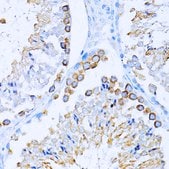

Anti-CD63 antibody produced in rabbit

IF, IHC, WB

immunofluorescence: 1:50-1:200, immunohistochemistry: 1:50-1:200, western blot: 1:500-1:2000